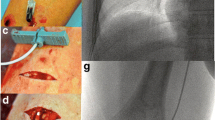

Most procedures (25/35) were performed under local anaesthetic without the need for further sedation. Six patients required sedation with intravenous 2 mg midazolam and four procedures were performed under general anaesthetic. No sedation or anaesthesia-related complications occurred. Different port devices were used, most of them (3/4) approved for high-pressure injections (P.A.S. Port T2 POWER P.A.C., 6F; Smith Medical MD, St. Paul, MN; Celsite Babyport 4.5 F; B. Braun Medical, Boulogne Cedex, France; Celsite, 6.5F; B. Braun Medical, Boulogne Cedex, France; Vital Port Mini System, 5 F; Cook, Bjaeverskov, Denmark). The heights of the port chambers ranged from 7.2 to 13.7 mm. Puncture and implantation sites were sterilely prepared (SkinseptG, Ecolab, Austria), and draped. Additionally, a blood pressure cuff was placed on the upper arm. Under ultrasound control and with the blood pressure cuff inflated below the systolic pressure, the basilic vein (at the distal upper arm) was punctured using an 18 G needle. In this context, a sterile covered high-frequency linear array (8 MHz) probe was utilized (Siemens ACUSON Freestyle). The orientation over the vein was at the discretion of the performing interventional radiologist, although a transverse orientation was used by most. The needle was placed in the middle of the transducer, advanced through the subcutaneous tissue, then the anterior vessel wall punctured under sonographic control. Just before penetrating the anterior vessel wall, it proved beneficial to reduce the needle angle, especially in more superficial veins. With the blood pressure cuff still inflated, either the needle sheath was directly advanced, or alternatively, a 0.014-in. nitinol guidewire (Medtronics, Minneapolis, MN, USA) was inserted prior to guidewire-supported insertion of the sheath. In cases of a noncompressible or small diameter basilic vein (<2 mm), the cephalic or brachial vein was used for venous access. After successful vein puncture, a 0.035-in. guidewire was introduced, with advancement through the vein fluoroscopically guided. The preference for the basilic vein is based on its relatively straightforward accessibility for puncture and subcutaneous tunneling, as well as the low risk of inadvertent arterial puncture or damage to the median nerve. Local anaesthetic was applied to the vascular access site, a small incision was then made followed by wire-supported exchange of the introducer needle for a peel-away sheath. In 31 procedures (88.6%), intravenous antibiotic (a first- or second-generation broad-spectrum cephalosporin) was administered periprocedurally via the sheath for infection prophylaxis. In patients allergic to penicillin or other antibiotics, the choice of an alternative antibiotic was made by the referring physician. Patients already receiving appropriate antibiotic therapy for another purpose received no further prophylaxis. Subsequently, local anaesthetic was applied on the proximal lateral forearm distal to the cubital fossa and in the location of the intended catheter tunnel. A 2- to 3-cm wide incision was made at the anesthetized site and a subcutaneous pocket for the port chamber created by means of a blunt dissection technique. Following this, the catheter was introduced via the peel-away sheath and placed in the superior vena cava under pulsed fluoroscopic guidance (7.5 pulses per s). In cases of difficult placement of the catheter within the superior vena cava, it often proved beneficial to advance the catheter with the patient’s head rotated toward the contralateral side while inhaling deeply. If these strategies still failed to allow catheter placement, a hydrophilic guidewire with a J angled tip was advanced through the catheter lumen into the superior vena cava and the catheter was placed over the wire. After tunneling the distance between the vascular access site and port chamber pocket, the final catheter position was achieved. The catheter was then shortened to an adequate length and connected to the port chamber, which was subsequently implanted subcutaneously. Port chambers were not routinely fixed with sutures in the subcutaneous pocket. The pocket was closed by means of subcutaneous (resorbable 4–0 Vicryl) and cutaneous sutures (3–0 Prolene). Closure of the incision at the vascular access site was performed with a single cutaneous suture. Using the included port-puncture needle, the port system was accessed, and the ability to aspirate blood was confirmed. Finally, the correct catheter position and connection to the port chamber were verified fluoroscopically with the injection of a small volume of contrast agent (Imeron 300; Bracco Imaging, Milano, Italy) (Fig. 1). The port system was then carefully flushed and locked with heparinized sodium chloride. Removal of cutaneous sutures occurred after 10–14 days. Patients and their parents were advised to contact the outpatient clinic immediately at the onset of any signs of infection. According to our in-house guidelines, a heparin lock is performed after each use of a port system. The approach outlined above did not change substantially over the study period.

Port implantation in the left forearm in a 16-year-old girl with a rhabdomyosarcoma. a Posteroanterior fluoroscopy confirms correct placement of the port catheter at the level of the central superior vena cava, just above the right atrium. b Oblique projection fluoroscopy image shows an implanted port chamber, with the port-puncture needle inserted in the proximal lateral forearm distal to the cubital fossa. Injection of a small volume of contrast agent proved the correct placement and connection of the port system